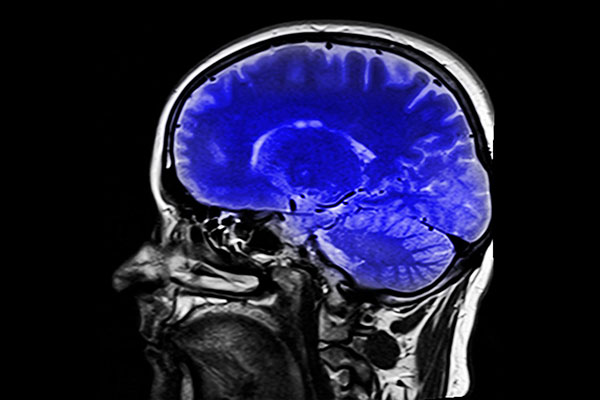

![]() 新研究表明,我们功能性磁共振成像技术(fMRI)的算法可能不对——研究人员在fMRI专用软件中发现一个算法错误,这个错误可能导致过去15年中关于人类大脑活动的研究变成一纸空文。 目前,研究大脑活动的最佳方式是功能性磁共振成像技术(fMRI)。fMRI是如此好用,以至于我们对其相当依赖——当然,只要fMRI准确又可靠,这也不是什么坏事。fMRI用于观察人们运动、游戏、恋爱以及用药时大脑的变化,一旦其出现问题,多年来的科研成果都会受到质疑。为了测试fMRI的功能,来自瑞典林雪平大学的研究人员进行了一场规模史无前例的试验,然而试验结果并不乐观。 研究人员写到:“尽管将fMRI作为研究脑功能的手段十分普遍,但是其用到的统计学方法几乎从用真实的数据验证过。” 由安德斯·伦德带领的研究队采集了数据库中499名来自世界各地健康的人处于静息状态时fMRI的检查结果,并将其分成20组,之后他们将各组互相比较,得到了惊人的三百万个随机对照。他们用这些配对来测试最著名的三个分析fMRI的软件——SPM,FSL和AFNI。 研究队伍期待看到软件之间的差异(约5%),然而实验结果令他们大吃一惊:软件的假阳性率达到了70%。这意味着软件有时会错得离谱,就算大脑处于静止状态时也会显示有活动——也就是说,显示出来的活动是软件算法的产物,而不是被研究的大脑真的处于活跃状态。 “这一研究结果导致40000个fMRI研究的结果受到质疑,也可能会对神经成像结果的解释造成巨大冲击。” 他们确认其中的一项错误在15年前就已经在系统中了,2015年5月研究队伍已经开始撰写论文时,这一错误才得以改正,但是该研究依旧令那些前期基于fMRI的研究受到质疑。 那么,这一研究方法到底有什么错误呢?fMRI的工作基于一个巨大的磁场,磁场在穿过人体时会捕捉到大脑局部血流的变化,这些微小的变化代表大脑特定区域活动的增加或减少,软件也是根据这一原理进行解析的。但问题在于,观察数据时,科学家看到的不是真正的大脑——他们看到的大脑的图像由无数的“立体像素”组成,之后通过软件编译出来,理查德·查温这样对登记簿网说道。 “与人类不同,在扫描立体像素时,软件寻找的是集束,”Chirgwin说,“如果有人说‘科学家知道接下来会动一动胳膊:图像就是证据’时,他们其实是在对统计学软件告诉他们的信息进行解析。” 由于fMRI使用价格较高,研究使用的样本量通常较小,也只有极少(如果有的话)的研究会进行验证性试验以确认结果。目前,可用于验证的手段也十分有限。 fMRI自90年代初投入使用后,在确认试验结果时,神经科学和心理学家就面对着巨大的挑战。但是Eklund相信随着fMRI的检查结果可以在网上自由获取,以及确认方法的不断发展,确认性试验会越来越多,人们也会及早发现软件中的错误。 “过去用一台电脑分析结果可能会需要10到15年的时间,”伦德说,“如今,由于显卡的使用,分析所需的时间从10年降到20天。” 那么40000篇可能有问题的论文怎么办?我们能做的只有重复试验,看看哪些是对的哪些是错的。(蝌蚪君编译自zmescience,译者 当当) |